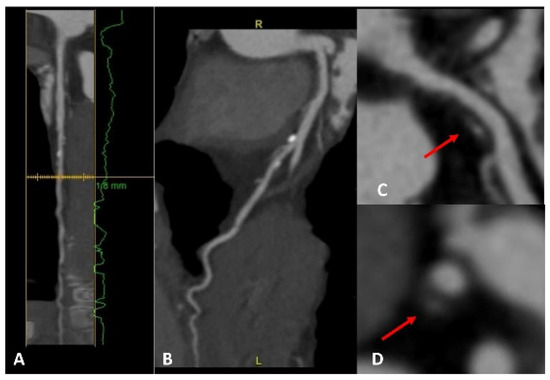

Another imaging technique that may play a prominent role in the future is cardiac magnetic resonance imaging (CMR). Indeed, CMR imaging has become an essential tool in diagnosing and managing cardiovascular diseases. It provides precise information on the structure and function of the heart, including the size and thickness of the heart walls, stroke volume, as well as any abnormalities in the heart muscle [37]. Thus, CMR can be used to detect early signs of myocardial damage or fibrosis, which may indicate an increased risk of heart failure or sudden cardiac death [38] (Figure 2). Consequently, CMR can be used to guide the implantation of an Implantable Cardioverter Defibrillator (ICD) for primary prevention [39]. Additionally, CMR can be used to assess valve function and identify structural abnormalities associated with a higher risk of cardiovascular events [40]. Overall, CMR has the potential to play an important role in primary prevention by providing more accurate risk stratification and guiding personalized management strategies for individuals at increased risk of cardiovascular disease. However, there is a lack of evidence on this topic, and the use of CMR to guide ICD implantation for primary prevention needs to be tested in RCTs. Notably, the ‘Cardiac Magnetic Resonance Guidance of Implantable Cardioverter Defibrillator Implantation in Non-ischemic Dilated Cardiomyopathy (CMR-ICD)’ trial is slated to complete recruitment by November 2023. This study is poised to shed light on the potential benefits of CMR for primary prevention to guide the implantation of ICD. The rationale is that CMR allows a meticulous assessment of cardiac functionality, morphology, and tissue characteristics [41]. The prospect of leveraging CMR, including the evaluation of late gadolinium enhancement (LGE), holds promising implications for enhancing risk stratification and decision-making in this cohort. The feasibility and cost-effectiveness of CMR compared with other imaging modalities also require evaluation.

Figure 2.

A case of a patient with a family history of sudden cardiac death, with frequent but isolated ectopic ventricular beats. Cardiac MRI was completely normal, with no evidence of myocardial fibrosis. (A). 4 Chamber view; (B). 2 Chamber view; (C). 3 Chamber view.